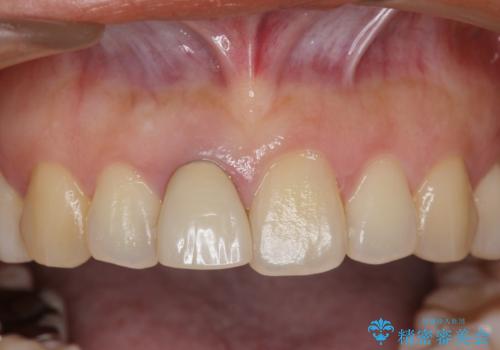

- 幼少期に前歯をぶつけて歯が折れ、神経の治療・クラウン治療を行った。グラつきと見た目の改善を希望して来院されました。

精密な仮歯をいれ、歯周組織を整えるとともにファイバーコア築盛、シェードテイキングを行い見た目に自然なジルコニアクラウンを製作していきます。